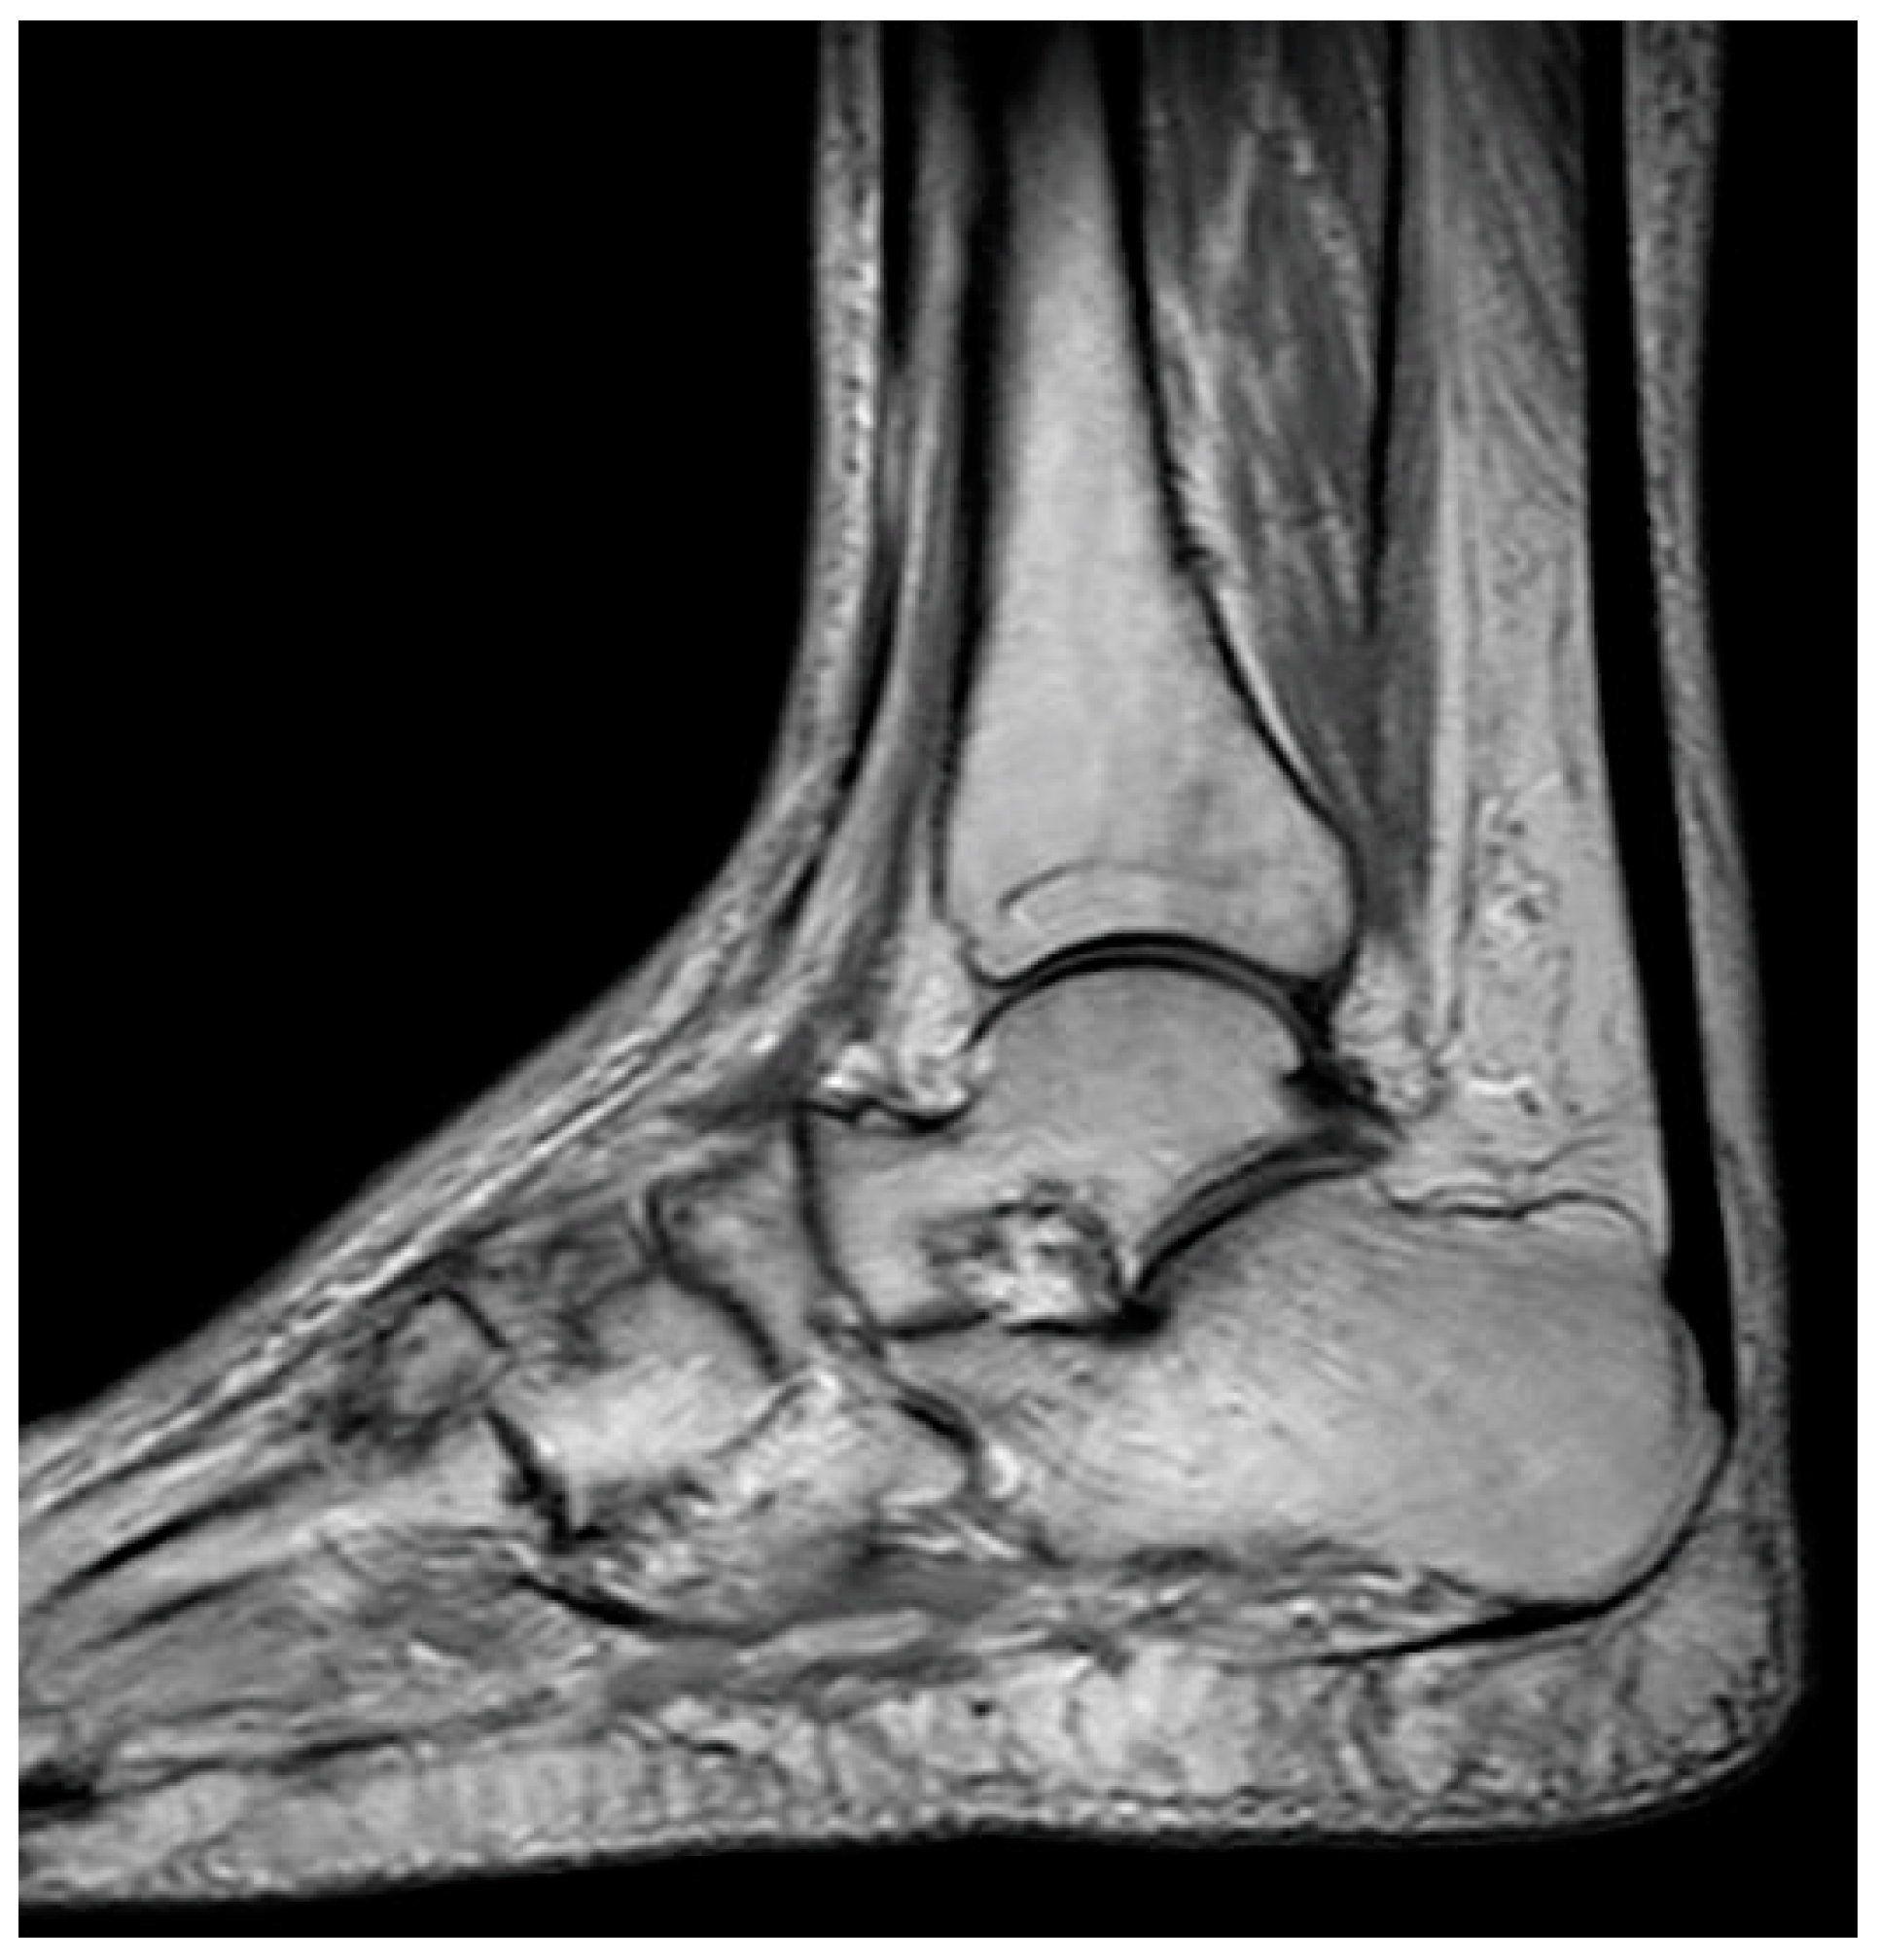

| MRI features | T1-weighted images display a single-density, low-signal intensity line. T2-weighted images display a high-intensity line with early necrotic-viable bone interface. | In T1-weighted images, the progeny is typically hypointense. In T2-weighted images, the progeny is mostly heterogeneous; this sequence can assess the integrity of articular cartilage, reactive marrow edema in the parent bone, and fluid or cystic changes at the parent-progeny interface. |